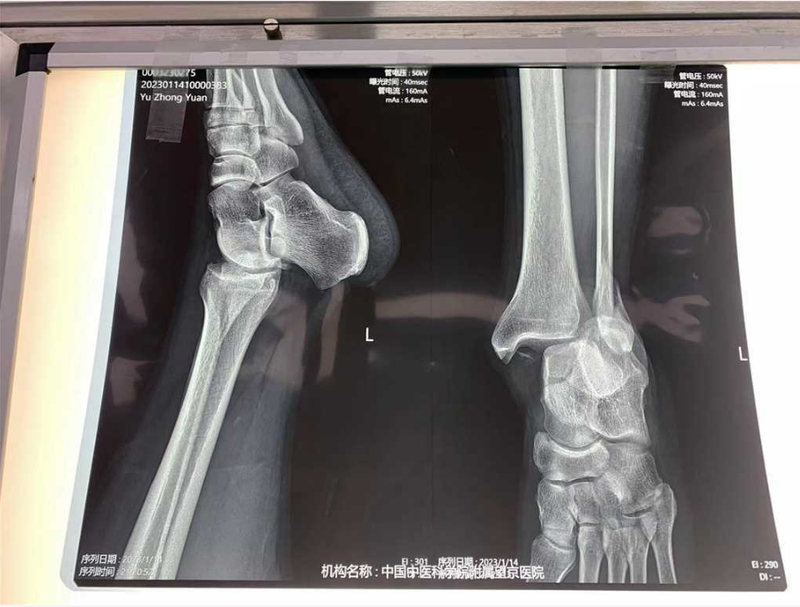

2// 踝关节

本病例由中国中医科学院望京医院骨关二提供(术者:支架主任蒋主任)

【基本资料】患者,男,41岁

本病例踝关节骨折。手术名称:左踝关节骨折外固定支架手术

【治疗后影像】